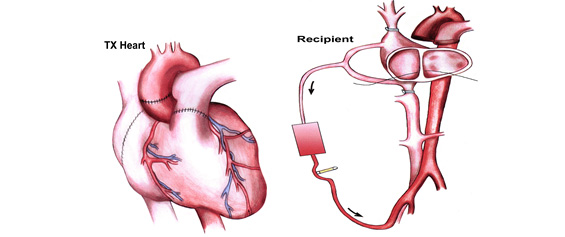

二、異位心臟移植手術:

病人本身的心臟並不切除,仍存在之功能尚可繼續利用,而植入之心臟則成為新的助力;原來的心臟保留在原位,再把捐贈的心臟置於病人心臟之右邊,把兩個心臟的左心房、右心房、主動脈及肺動脈連接相通。